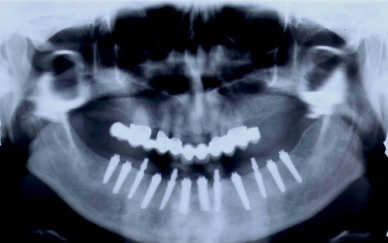

Bezzubá čelist je hlavní indikací pro ošetření pomocí implantátů. Zejména celkové zubní náhrady v dolní čelisti mají velice nízkou stabilitu a držení díky velkému úbytku kosti.

S pomocí zubních implantátů můžeme díky různým kotevním systémům (třmeny, kulové hlavy, Locatory) zajistit stabilitu a držení protézy nebo při použití většího počtu implantátů zhotovit pevné náhrady – můstky nalepené nebo našroubované na pevno na implantáty.

S těmito typy náhrad můžeme dosáhnout perfektní funkci, výbornou estetiku, fonetiku a současně zajistit u pacienta možnost dobré hygienickou péče a čištění, která je pro životnost implantátů velice důležitá.